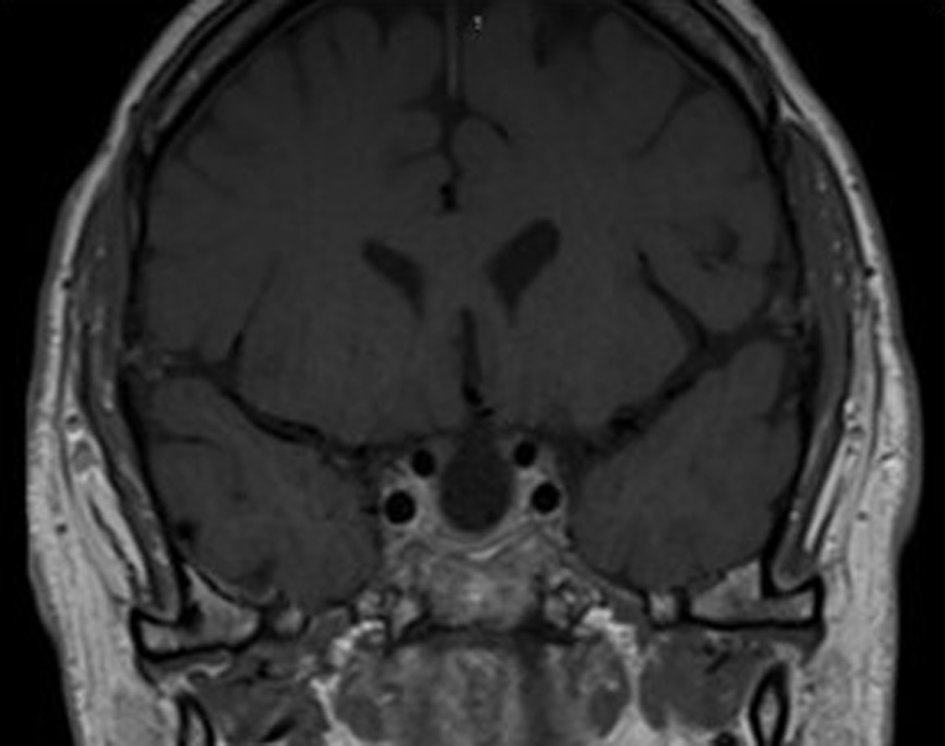

Mild postoperative hyponatremia was due to the syndrome of inappropriate antidiuretic hormone secretion (SIADH), which improved with fluid restriction. Perioperative intravenous hydrocortisone 50 mg 6th hourly coverage was administered to prevent adrenal insufficiency. A low T4 level necessitated the administration of L-thyroxine (50 mcg once daily), but cortisol response was adequate and he was discharged with follow-up after 6 weeks. At follow-up, repeat anterior pituitary hormone profile test showed low TSH, T4, LH and testosterone levels, with a good response to the short synacthen test. Postoperative follow-up MRI after 3 months showed a near complete resection of the tumour (Figure 3).